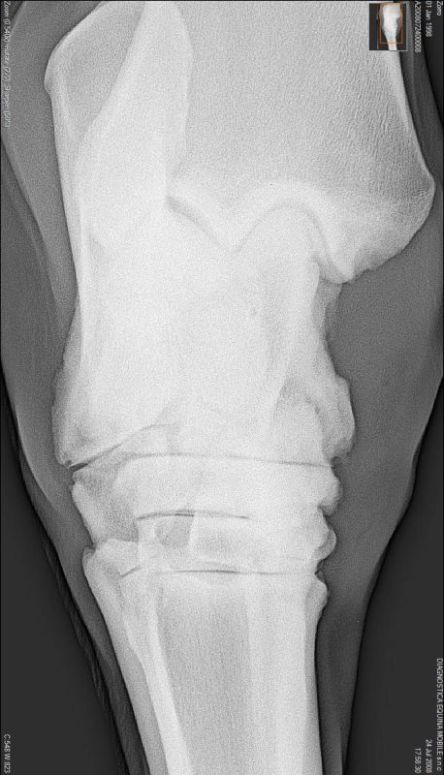

Briefly the radiographs show wear and tear changes common in many older working horses: osteophytes (bone spurs), calcification on the anterior of the pastern, partial calcification of the collateral cartilages. I do not see any definitive congenital defects. The talus of the hock has some odd irregularity but I don't review many digital radiographs and this could be a range of normal for it.

It depends on what you mean by arthritis. Do I see any lesions that correlate with painful arthritis 100% of the time? The answer is no. But yes there are osteophytes visible in both the tibiotarsal and proximal intertarsal joints (the upper two). The talus within the tibiotarsal joint also show evidence of bony resorption and production. These are markers for the presences of osteoarthritis.